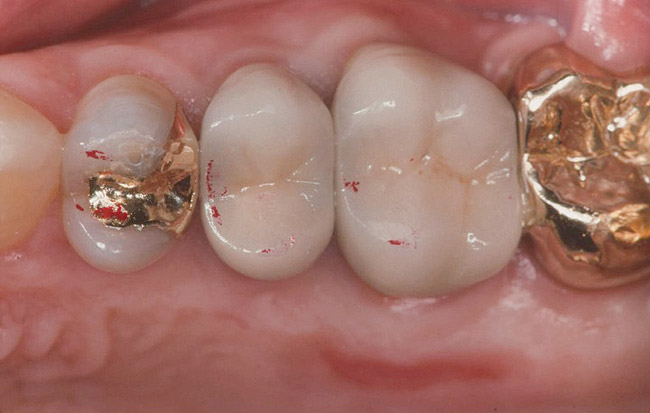

Figure 4. Occlusal contacts occur generally on the posterior teeth, most often on the first molars, followed by the second molars and premolars.

Figure 4

Static Occlusal Contact

Loss of tooth contact or near contact78,79 on one quadrant of the mouth has the potential for dysfunction and perhaps even lasting damage to the musculature, not just on the noncontact side, but on both sides.80 Tooth contact during maximal force chewing is the same as in static maximum force intercuspal contact,81 indicating the role stable functional tooth contacts play in optimal muscle function. However, not all of the teeth have contact in maximum intercuspation.82,83 Moreover, most of the contacts that do occur are in the molar region, and, not surprisingly, the greatest forces of contact are also found posteriorly (Figure 4).84 It can be inferred that one of the functions of the posterior teeth is to hold the infero-superior component of vertical dimension, and in some cases (ie, group function), the medio-lateral vector as well.